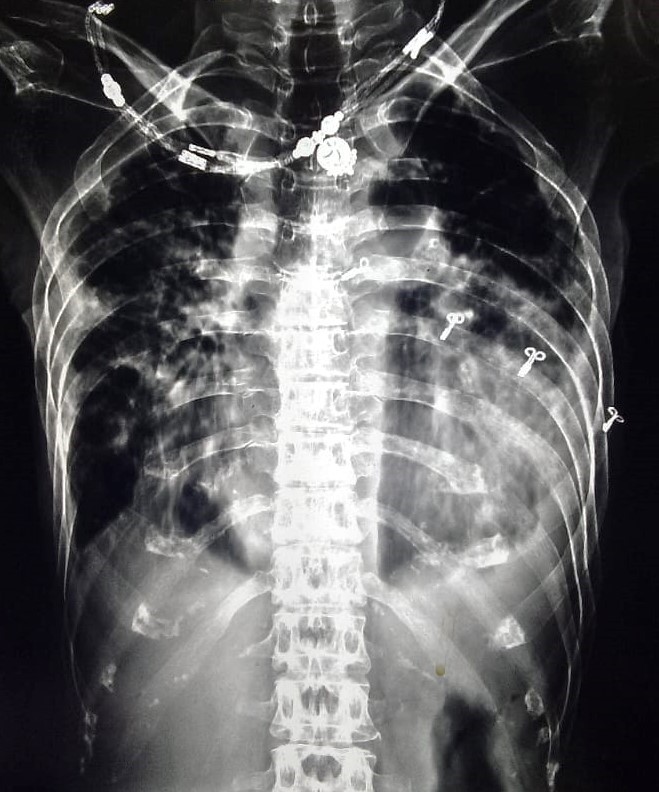

| 31 | IGGMC, Nagpur, Nagpur | P2 | 29-4441 | Shaina Parveen | Consent taken on Paper | 52 Yrs. |

Provisional Diag : Post TB Treatment Follow-Up

Final Diag : Pulmonary Tuberculosis (clinically diagnosed PTB) |

TB Case (Confirmed) | Bilateral Multiple Ill-Defined Opacity Present, Hyper Infiltration Present, Bilateral Lower Zone Haziness Present | Abnormality visible on x-ray |

View |

|||